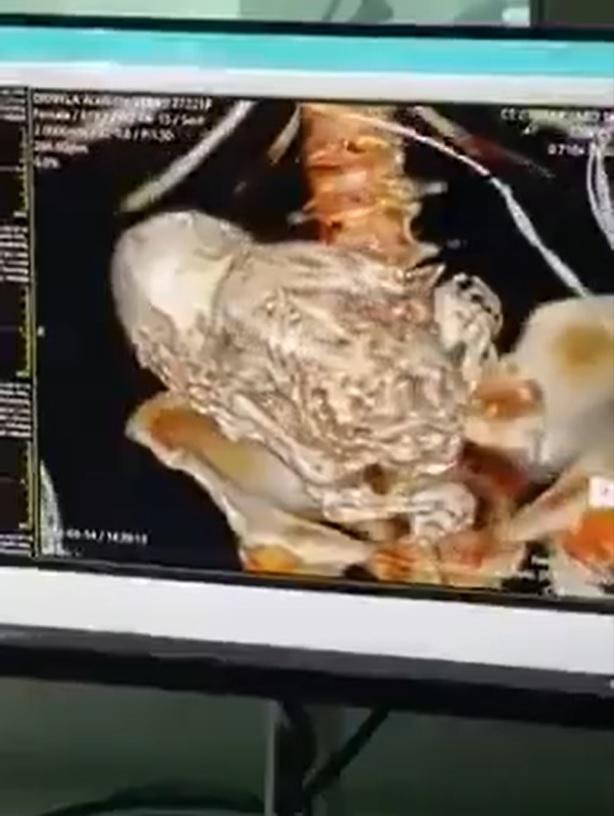

Bajo ese contextos, los médicos le hicieron una tomografía para saber qué es lo que estaba pasando en su cuerpo. Cuando obtuvieron los resultados, no podían creer que la mujer tenía un feto calcificado en su interior.

Los expertos calcularon que la mujer cargó con el también llamado "bebé de piedra" desde su último embarazo, entre hace 30 y 40 años atrás, por lo que el equipo médico de urgencias procedió a realizar la extracción quirúrgica del feto con la intención de "controlar la grave infección que sufría la mujer y que amenazaba con su vida", según contó El Mundo.

En primer lugar, un feto calcificado es una complicación que resulta luego de un embarazo no viable, cuando un óvulo se fertiliza fuera del útero. Científicamente recibe el nombre de litopedion, pero también recibe el nombre de feto calcificado, momificado o bebé de piedra.

No obstante, con el pasar del tiempo, "el sistema inmunológico de la madre eventualmente reconoce al feto como un objeto extraño y para protegerla de una posible infección, reacciona revistiendo el feto con una sustancia rica en calcio mientras ocurre la deshidratación de los tejidos. Se forma una pared mediante el depósito de calcio, el feto se convierte en un litopedion momificado".